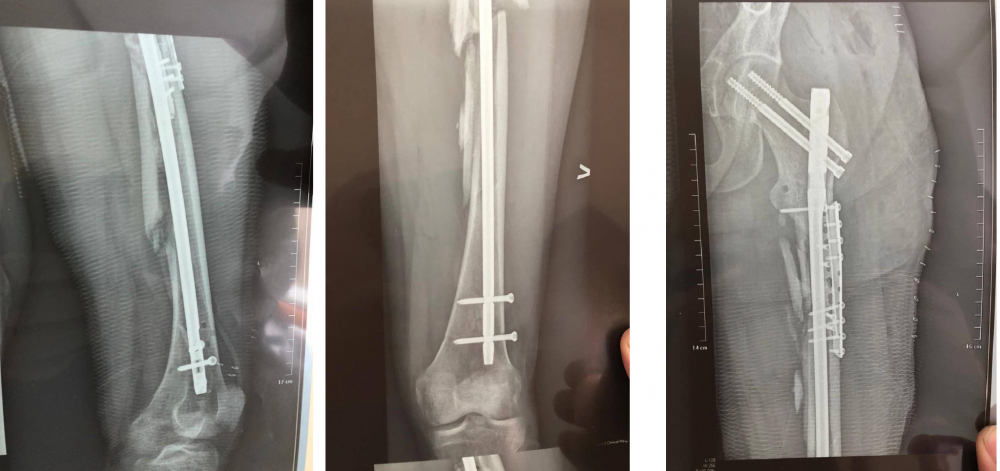

Також в розпорядження ми отримали рентген-знімки травми тіла, зокрема ноги, яку лікарі збирали фактично по частинах за допомогою імплантування металевих шприх. А ще сюди додайте металеві пластини в голові – невже це легкі ушкодження?!.

рентген-знімки Олександра Мізраха внаслідок ДТП